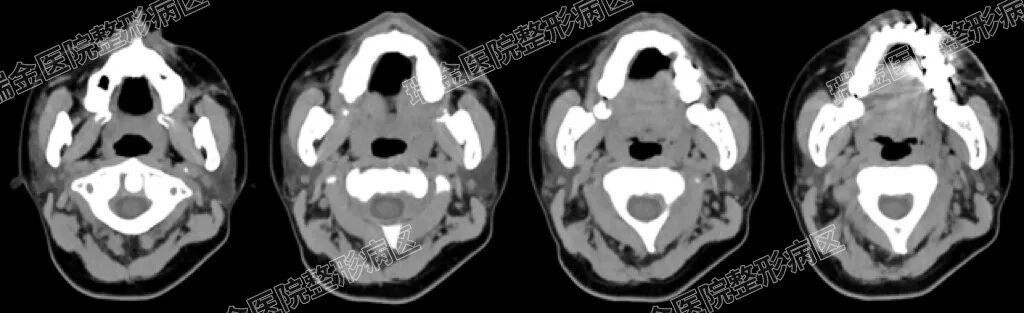

“面部不是简单的‘填坑’,得先搞清楚‘坑’是怎么来的。” 易磊副主任医师团队接诊后,并没有急于制定方案,而是先给小琳做了颌面部 CT 检查。结果显示,小琳左面部不仅有大量瘢痕组织,皮下脂肪还因当年的外伤坏死,受伤后皮肤和深层肌肉也紧紧粘在了一起。结合小琳的多次手术史和对 “不留疤” 的需求,易磊医生团队最终定下方案:面部微针松解瘢痕+腹部吸脂+自体脂肪移植。

CT影像图

该方案可以解决粘连的根源,并最大程度减少伤口。肚脐周围的皮肤隐蔽,2毫米的小口藏在肚脐里,愈合后根本看不出来,易磊医生团队的方案特意考虑到“美观细节”。然而,面部血管神经密布,就像错综复杂的 “小路”,小琳这场微创手术,需要在毫米级的小孔进行,医生视野受局限,要靠术前评估“指好路”。“脸上的神经非常重要,稍有不慎一旦碰到,可能导致面部瘫痪。” 易磊医生解释,团队仔细分析CT影像,精准确定瘢痕粘连范围,更标注出重要血管、神经的位置,确保安全又有效。